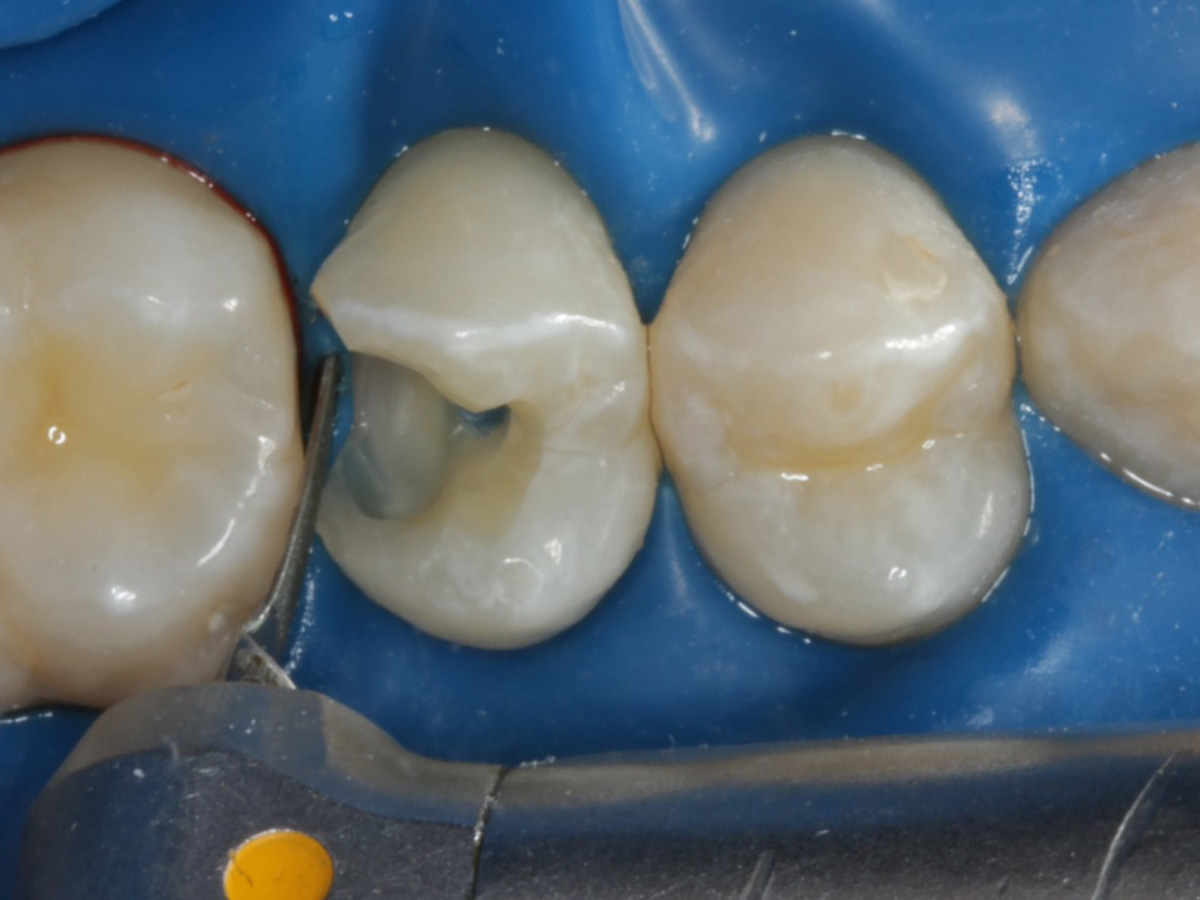

Abbildung 28

Kompositrestauration nach „Schachtverschluß“; keine Krone geplant